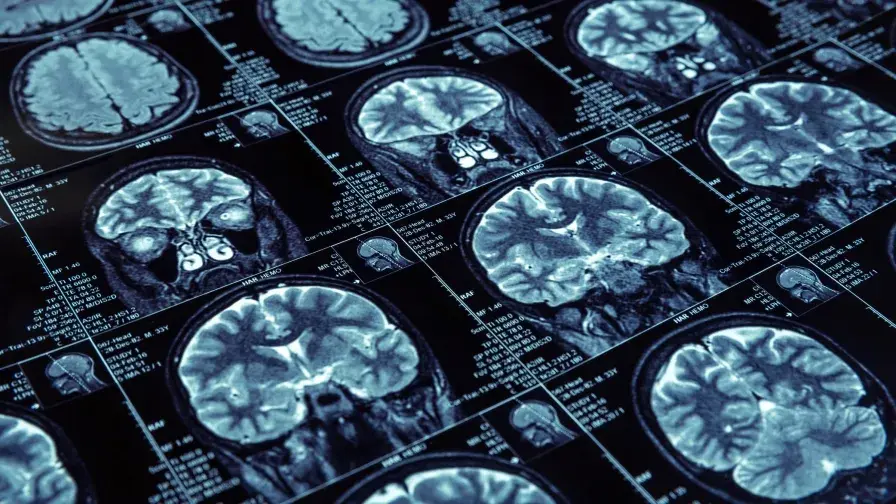

Alzheimer : l’étude INSIGHT montre l’existence de mécanismes de compensation chez les sujets porteurs de lésions pour maintenir leurs performances intellectuelles et mnésiques

L’étude, dirigée par le Pr Bruno Dubois a été menée par des équipes AP-HP, Inserm, CNRS et Sorbonne Université, au sein de l’ICM et de l’IM2A à l’hôpital de la Pitié-Salpêtrière.

• Elle vise à observer chez des sujets âgés de plus de 70 ans, bien portants et sans trouble cognitif, les facteurs de développement de la maladie d’Alzheimer.